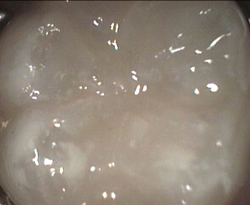

unusual wide but superficial decay after